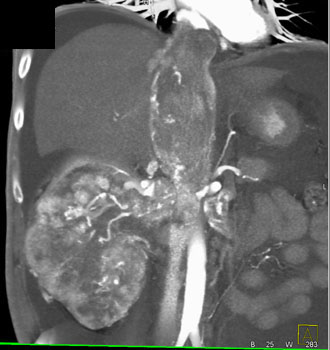

Question 7: 50ish year old male with increasing chest and abdominal discomfort. What is the most likely diagnosis in this case?

Diagnosis: Renal Cell Carcinoma Invades the Renal Veins and IVC

Differential Dx: Right Atrial Mass

• Intracardiac thrombosis

• Atrial myxoma (15% of myxomas)

• Metastases including direct tumor extension (renal,adrenal and hepatoma)

• lymphoma